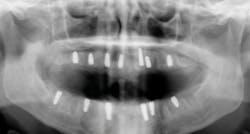

Another reason immediate placement is advantageous is that once the extraction is complete, the hole is usually already in the proper place for the implant. You may have to redirect your osteotomy slightly palatally, mesially, or distally, but the socket serves as an excellent guide for placement. In some cases, especially premolars, you can use an implant with aggressive threads to place without any osteotomy at all. You can engage the mesial and distal walls to achieve primary stability. This greatly shortens the appointment time, lowers risk, and increases patient satisfaction. Figures 1 and 2 show a MorsTorq in site No. 21 that was placed after an atraumatic extraction during my most recent two-day Louisiana Implant Institute course. Note the sharp threading on the MorsTorq, which allows for optimized immediate placement performance.There are some circumstances where immediate placement is not desirable. If the socket is too large to engage the mesial and distal walls and vital anatomical structures are located just apical to the socket, immediate placement is not recommended. Chronically infected sites also present a higher risk for immediate placement. If you can completely rid the socket of all soft tissue and the patient has the appropriate antibiotics onboard, it is possible. However, most of these cases are more predictably treated with early placement (waiting four to six weeks without grafting) or delayed placement (three to six months with grafting).